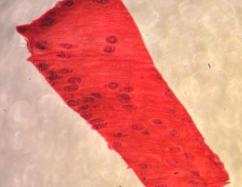

trichinella spiralis larwy otorbione